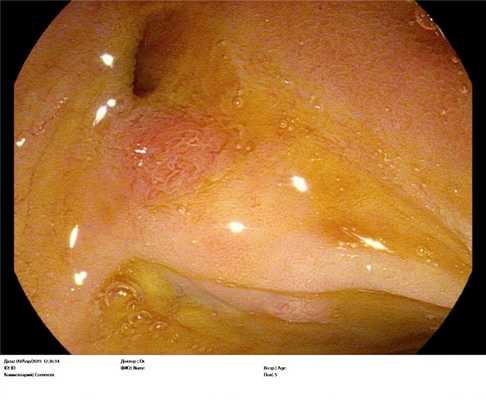

Рельеф слизистой оболочки терминального отдела подвздошной кишки. Гистологическое исследование от 18.02.2021 г. : Слизистая оболочка подвздошной кишки неравномерной толщины, с неравномерным расположением крипт. Ворсинки высокие, правильно ориентированы, выстланы зрелым эпителием кишечного типа. Имеются участки с низкими широкими ворсинками. В собственной пластинке умеренная лимфогистиоцитарная, эозинофильная инфильтрация, нейтрофильные гранулоциты отсутствуют. Межэпителиальные лимфоциты соответствуют норме. определяются участки с выраженной зрелой лимфоидной инфильтрацией и формированием лимфоидных фолликулов. В собственной пластине - выраженный фиброз. Заключение: Хронический илеит с участками атрофии и гиперплазией лимфоидной ткани, ассоциированной со слизистой оболочкой.